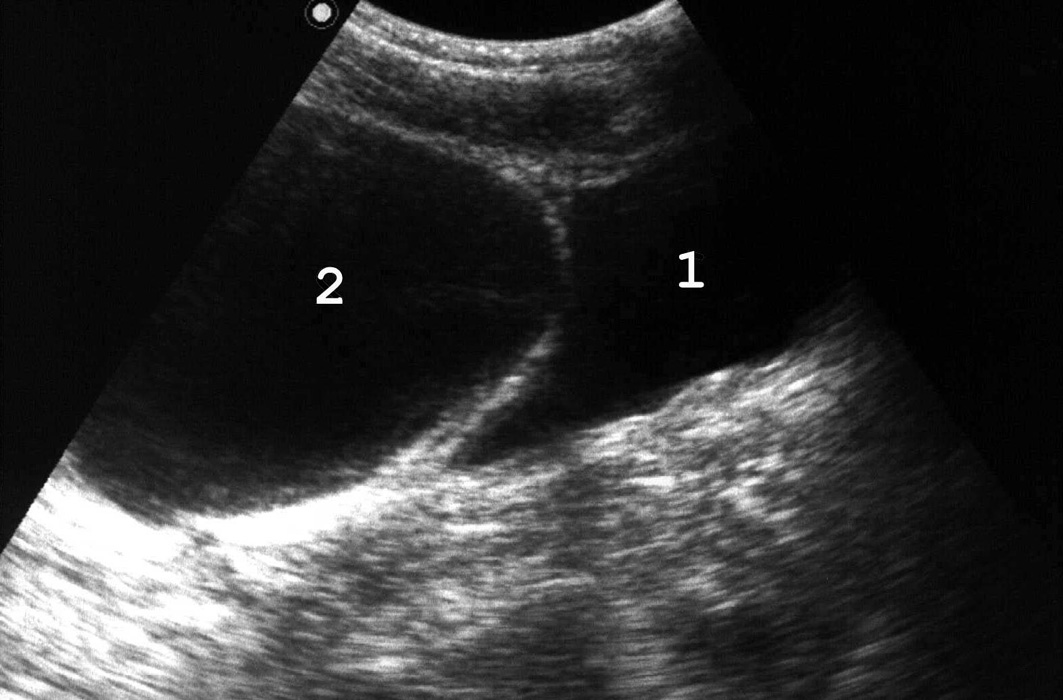

Рис. 5. При хронической задержке мочи вначале развивается гипертрофия мышечной оболочки мочевого пузыря: 1 − мочевой пузырь; 2 − увеличенная простата; 3 − утолщенная стенка мочевого пузыря. (Продольное сканирование, конвексный датчик 5 МГц, “Logiq-500”).